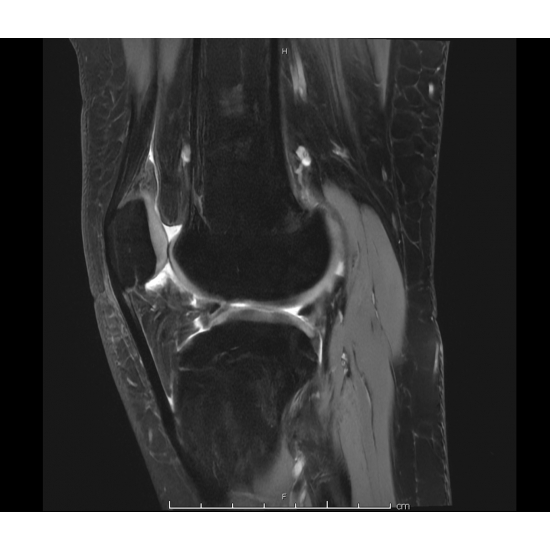

| Teenage Girl Knee-ding Some Stability - Page #3 | |||